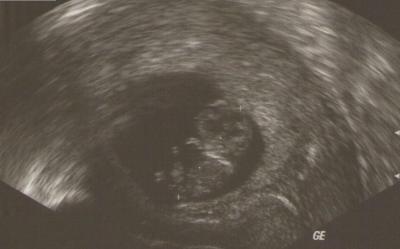

US-Bild vom Mini

Ich finde, man kann es recht gut erkennen .....sogar meine kleine Tochter konnte ein "Baby" sehen.

Oh ja, da kann man wirklich einen süßen Krümel sehen. Herzlichen Glückwunsch Alles Liebe Claudia